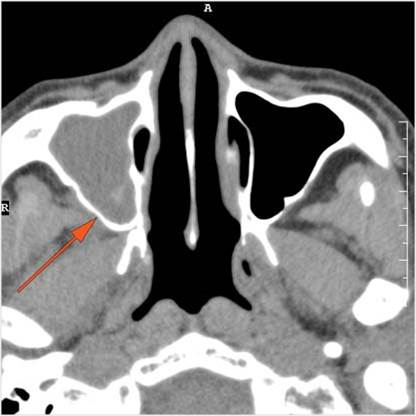

The fat pad posterior to the maxillary sinus and within the pterygopalatine fossa are infiltrated.